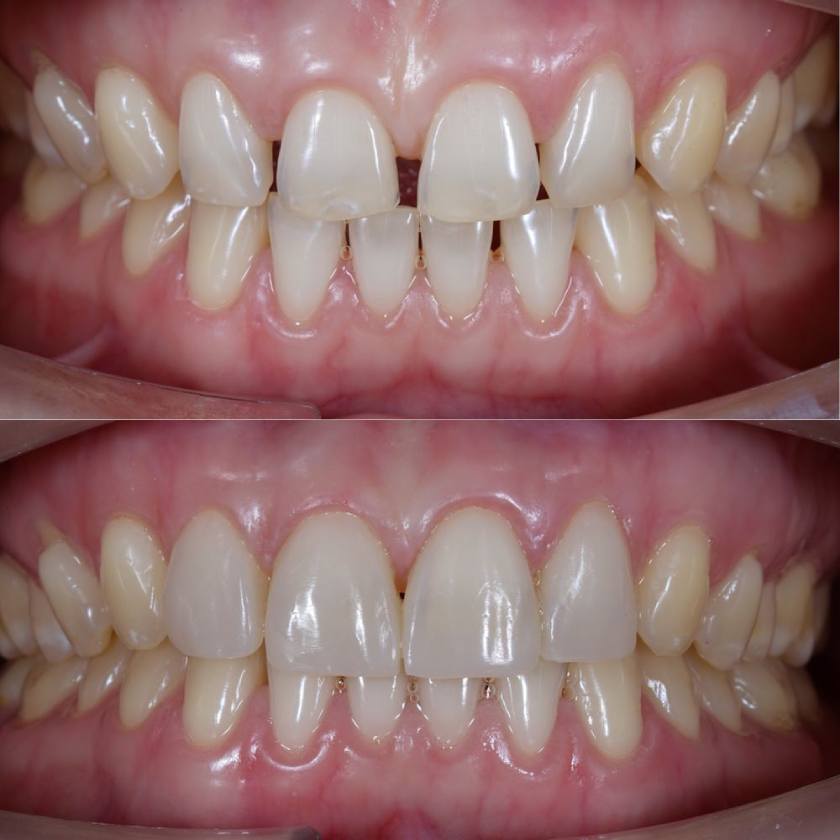

Hình ảnh trám răng thưa

Trám răng thẩm mỹ được áp dụng trong các trường hợp như răng bị sâu nhẹ chưa ảnh hưởng tủy răng, răng bị viêm tủy nhẹ, răng bị mòn men răng, răng bị nứt - mẻ - vỡ nhỏ do chấn thương hay va đập, răng bị hở kẽ nhẹ.